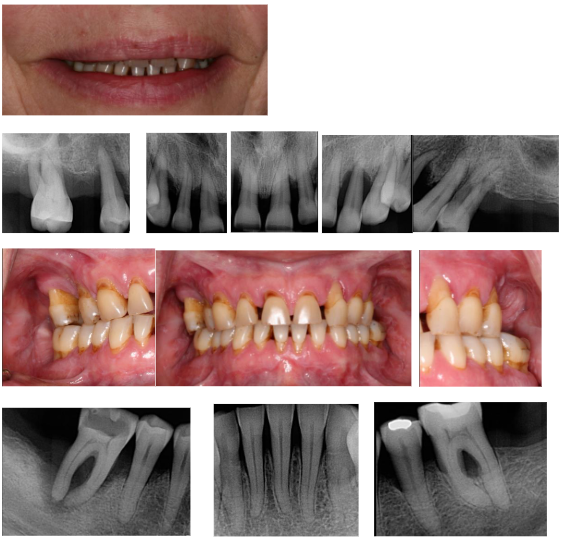

Case Presentation

A 53-year-old Caucasian female presented with a chief complaint of difficulty smiling, chewing, and speaking. Clinical examination revealed severe generalized periodontitis, posterior bite collapse, and multiple failing teeth. Radiographic evaluation confirmed significant alveolar bone loss and compromised tooth support. The patient’s medical history included vaping, anxiety, arthritis, osteopenia, and headaches. This complex medical history, coupled with the patient’s dental neglect, highlighted the need for a multidisciplinary approach involving collaboration with the patient’s physician and a focus on mitigating risk factors.